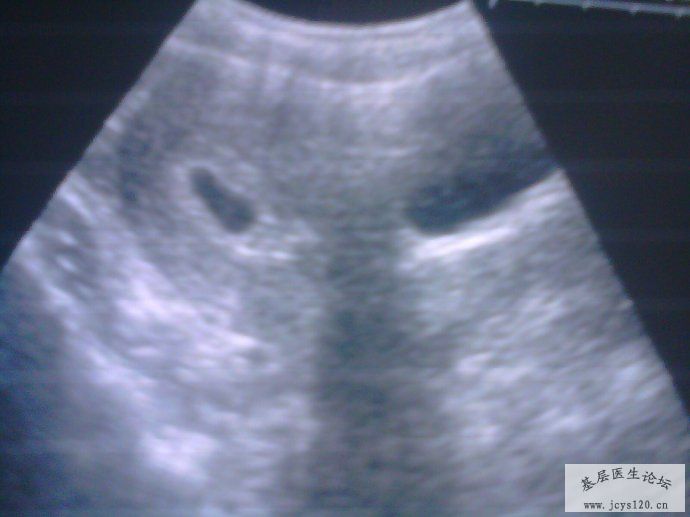

下午见阴道有出血,量不多,七点再次做B超,如图: